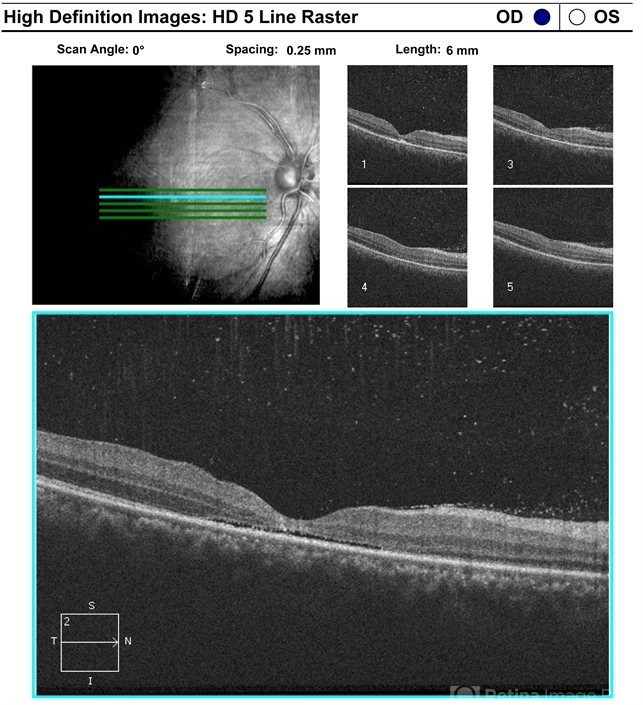

- Choroidal rupture subretinal and vitreous hemorrhage secondary to blunt trauma

- optical coherence tomography (OCT), blunt trauma, macular hole

Optical coherence tomography system

Cirrus HD OCT - Description

- One week after blunt trauma, closure of macular hole is seen, persistent thinning and subretinal fluid are observed. Vision is CF.